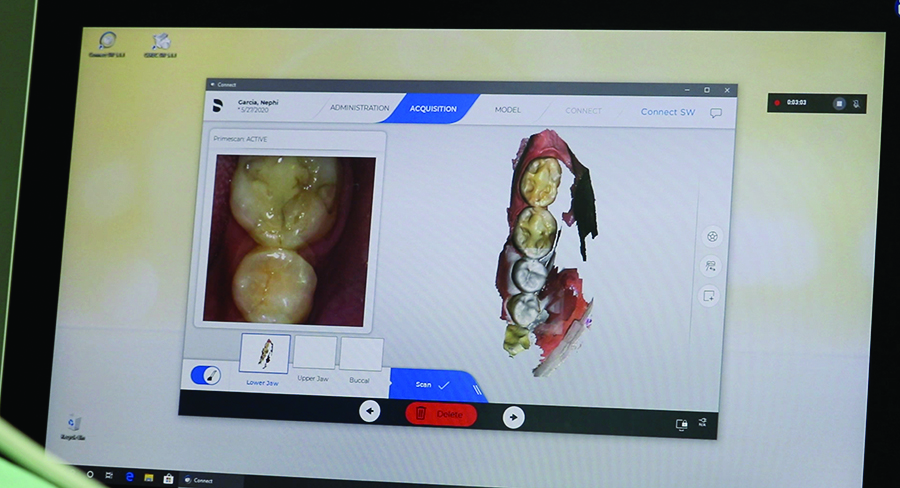

In the first session, we scanned the patient’s oral situation with Primescan. This is a standardized procedure for us because it allows us to accurately assess the intraoral situation, even in subgingival areas. It is also the starting point for further digital processes, such as treatment planning with the dental technician. We also took a 3D x-ray image and pictures of the patient’s face. Based on that, we talked through the treatment options as well as potential challenges with the patient.

Digital impression taking with Primescan is very accurate, the digital model is immediately available and can be discussed directly with the dental technician while the patient is sitting on the treatment chair, via a chat tool in the Connect Software. This was very helpful, because the technician could review the scanned data and request additional views or angles.

Scan of the intraoral situation with Primescan.

Fig. 6

Primescan recordings of the initial situation.

Planning and consultation based on Primescan images in the dentist/dental technician team.